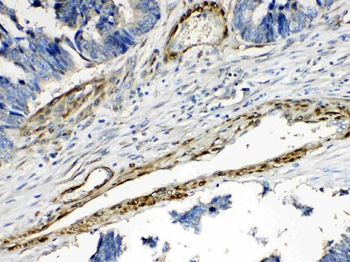

- Anti-GSTM3 Antibody [orb402287]

ELISA, IHC, WB

Human, Mouse, Rat

Rabbit

Polyclonal

Unconjugated

10 μg, 100 μg - Anti-S100 alpha 6/S100A6 Antibody [orb315184]